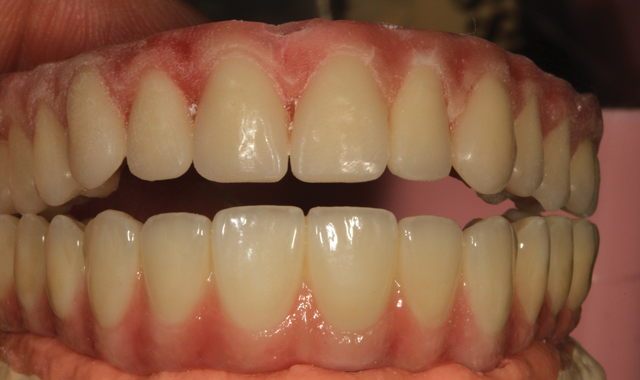

Fig. 16 Try-in the mouth

Final, upside down view of the six implant units (Fig. 16) follow.